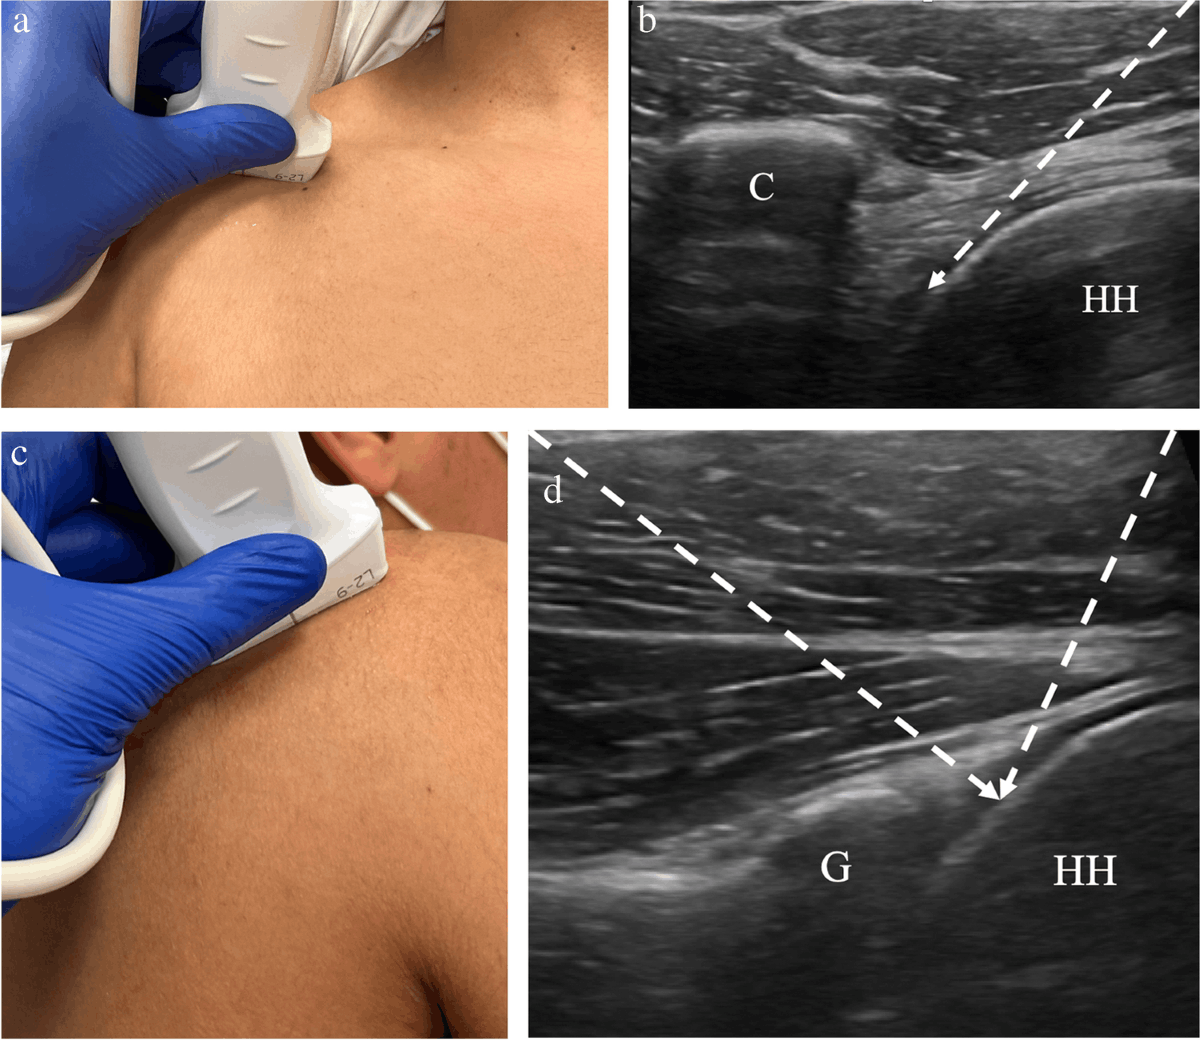

3. Ultrasound-Guided Corticosteroid Injections

Targeted injections under ultrasound guidance reduce inflammation and improve motion—particularly effective in the early stages of frozen shoulder.

Ultrasound guided injection for frozen shoulder treatment Phoenix A

4. Joint Hydrodilatation

This minimally invasive technique involves injecting sterile fluid into the joint capsule to gently stretch it. Often combined with therapy.